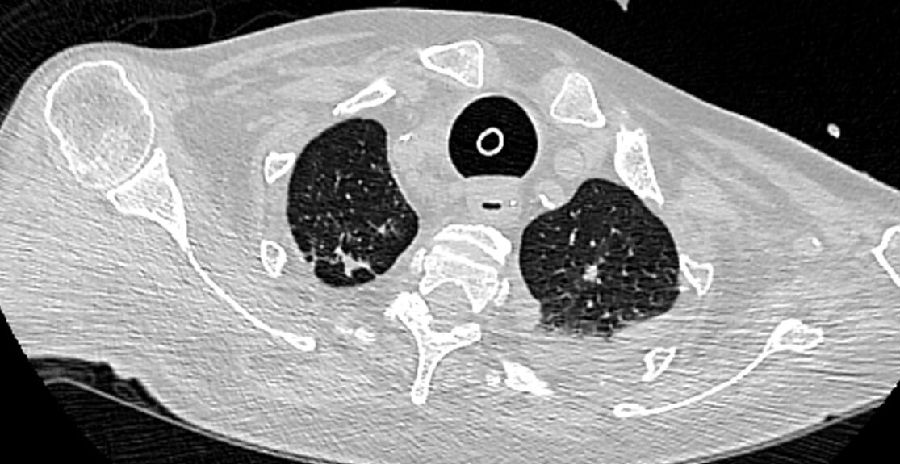

此例发生气管食管瘘的患者十分消瘦,气管-食管间软组织薄弱,当气管软化、破裂后很容易就累及到临近的食管,导致气管食管瘘。如果患者营养状况良好,气管-食管间软组织较厚,也许会是另一个结果。下图是另一位长期气管插管患者的胸部CT平扫图,可见气管已经出现了明显的扩张,但由于气管-食管间组织较厚,还未发生气管食管瘘。

图4 一名肥胖患者的胸部CT平扫图